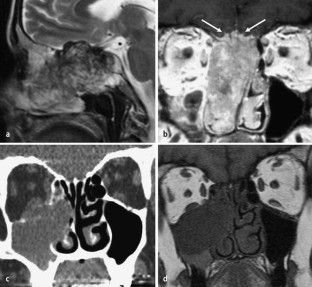

Abb. 2